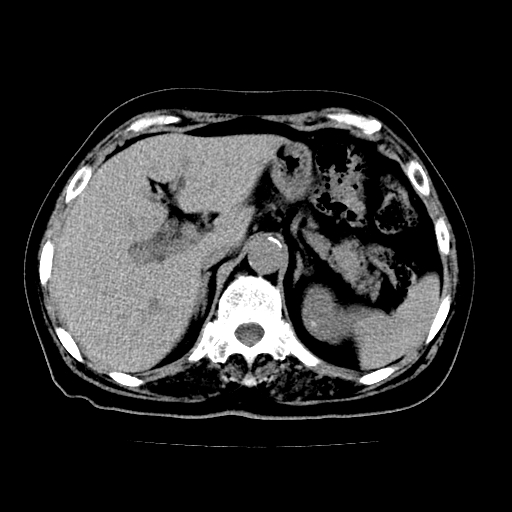

以下是引用lujiandong在2009-2-8 9:37:00的发言:[br]从所发的ct平扫图象上看,胆总管明显增粗,从上向下逐渐变细,是否有泥沙样结石,建议薄层重建;胰腺形态基本正常,左侧肾前筋膜轻度增厚。可以考虑:轻度单纯性胰腺炎,建议ct增强扫描。